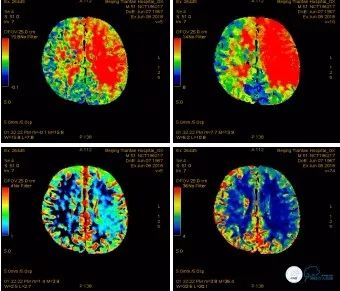

头CTP(2018-06-08):左侧大脑半球MTT、TTP明显延长,CBV略升高,CBF降低(图4)